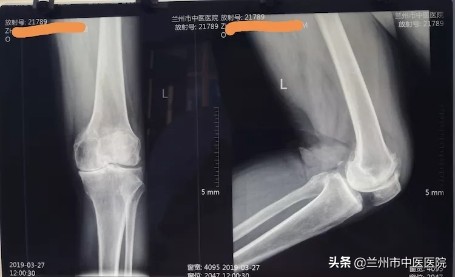

入院症见:左膝关节肿胀、疼痛,屈伸活动受限,上下楼梯困难,不能下蹲,行走困难睡眠差,食纳可,二便调。查体:左膝关节肿胀,屈伸活动受限,内侧间隙压痛(+),股骨内上髁压痛(+),髌尖粗面压痛(+),浮髌试验(-),髌骨研磨试验(+),入院后查左膝关节正侧位片及腰椎正侧位片如下:

风湿科李主任认真查体、阅片后提出:膝关节骨性关节炎临床上将其分为四期,该患者以左膝关节内侧间室退变为主,内侧间隙明显变窄,内侧半月板基本消失,关节面硬化,关节功能部分障碍,符合三期改变,患者曾就诊于多家医院,均建议手术治疗,由于患者经济能力及对于手术的恐惧心理,拒绝手术治疗。后经朋友介绍,张某就诊于我科,根据软组织外科学查体发现,患者腰骶部存在广泛压痛,尤以左侧腰部深层肌、腰背筋膜、髂胫束、臀上皮神经、髂后上棘、臀中肌、股骨内上髁、膝关节内侧间隙以及髌尖粗面压痛为甚。综合分析,该患者最早以椎管外腰骶部软组织损伤为主,其无菌性炎症反应产生剧烈的腰部疼痛症状,进一步引起腰骶部、臀部及大腿内侧肌群痉挛,继而出现“因痛增痉(挛)”和“因痉(挛)增痛”的恶性循环,久而久之,导致患者出现脊柱侧弯、椎体旋转、骨盆失稳。膝关节是人体负重关节,承受着人体的自身重量,腰骶椎及骨盆失稳会导致下肢力线发生改变,最终导致患者左膝关节受力集中于内侧,进一步加重了左膝内侧半月板磨损以至基本消失,如下图所示: